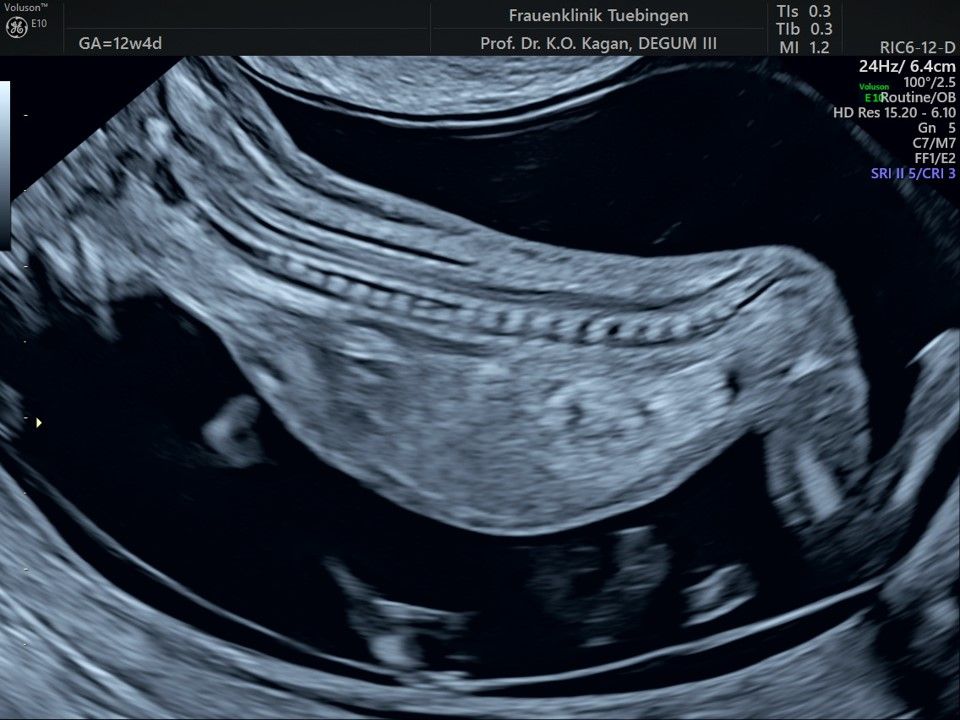

Das Ergebnis der Ultraschalluntersuchung ist wegweisend. Dabei wird der Fet vermessen, die Organe werden untersucht und die sonographischen Marker zur Risikoberechnung für Chromosomenstörungen werden beurteilt. Das sind: die Nackentransparenzdicke, Nasenbein sowie der Blutfluss in der rechten Herzhälfte und im Ductus venosus, einem Gefäß in der Leber des Feten.

Findet sich eine Fehlbildung oder ist die Nackentransparenzdicke deutlich erhöht, werden wir mit Ihnen eine Abklärung mittels Fruchtwasser- oder Mutterkuchenpunktion besprechen. Ob diese dann tatsächlich durchgeführt wird, müssen wir in einem gemeinsamen Gespräch klären.